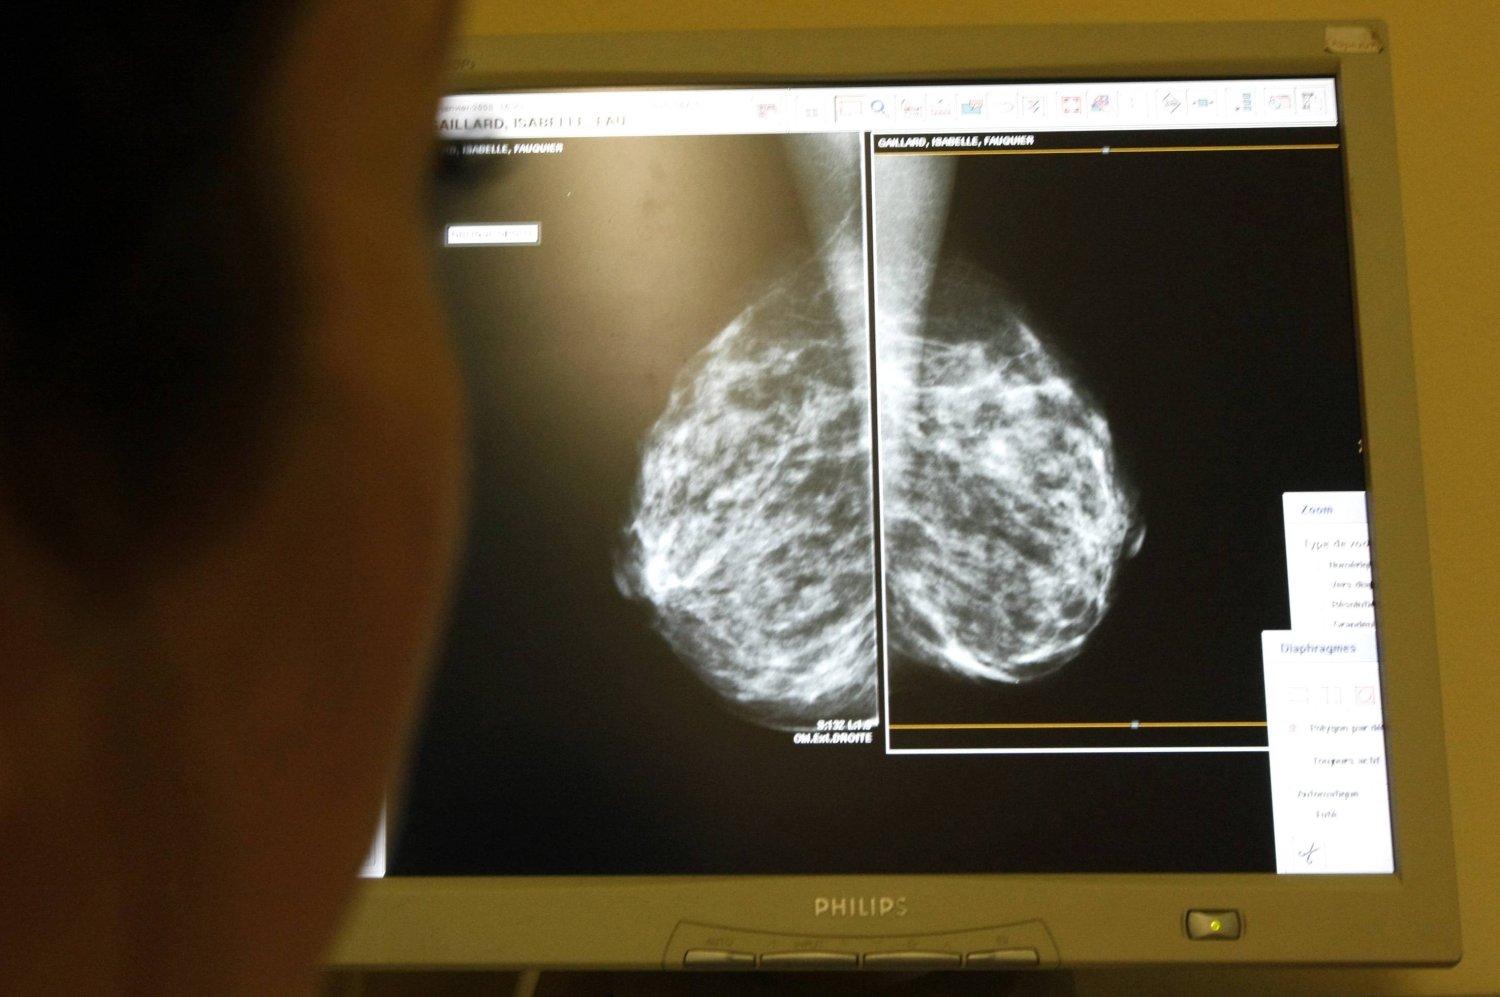

فحص ثديَي الرجل

لا توجد إرشادات رسمية لفحص الثدي الذاتي للرجال، ولكن يمكن للرجال اتخاذ خطوات استباقية لمراقبة صحة ثديهم من خلال تقنيات الفحص الذاتي المقترحة. يُنصح بإجراء هذه الفحوصات في نفس الوقت كل شهر، ربما نفس وقت فحص الخصية الشهري. ابدأ بالوقوف عاري الصدر أمام المرآة لفحص أي تشوهات مثل التورم أو الكتل أو الغمازات أو تغيرات الحلمة، مع وضع ذراعيك على جانبيك ورفعهما فوق رأسك. لإجراء الفحص اليدوي، استلقِ مع وضع وسادة تحت كتفك وذراع الجانب الذي تفحصه خلف رأسك. استخدم اليد المعاكسة للضغط برفق بأصابعك في دوائر صغيرة عبر منطقة الثدي بالكامل والإبط، وتطبيق ضغوط مختلفة، واضغط برفق على الحلمة للتحقق من وجود إفرازات. إذا اكتشفت أي تغييرات، فاستشر مقدم الرعاية الصحية الخاص بك.